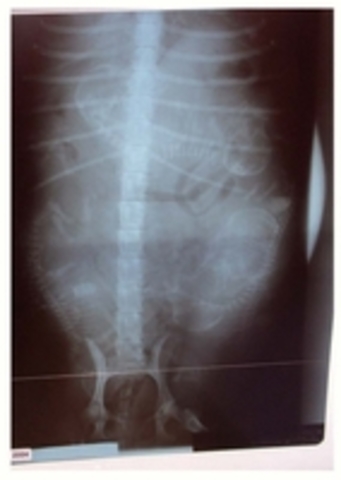

Día 50: Los fetos pueden visualizarse en una radiografía. Es posible contar el número de fetos. Las radiografías realizadas en este momento de la gestación

Día 53: preparar el ambiente. Ropa de cama: Temperatura 30ºC y recipientes con agua para mantener la humedad.